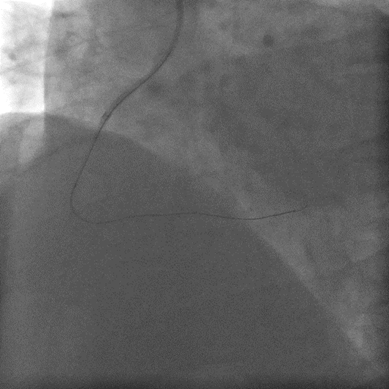

右冠迂曲,中段急性闭塞,可见血栓影。

AL1.0指引导管, Sion blue 导丝未通过,Fielder XT-R 达右冠远段。

抽吸导管未通过,Artimes1.5x15mm球囊@6-12atm。

Finecross交换sion blue导丝, Artimes 2.0x20mm球囊@6-12atm。

抽吸导管仍无法通过,双腔微导管于闭塞段内注射普佑克10mg。

Artimes2.5x15mm球囊@6-12atm。

右冠远段显影,双腔微导管送sion导丝至后侧支远段。

Excrossal 2.75x36mm@8atm 后侧支中段至右冠远段。

Apollo3.0x15mm、3.5x15mm球囊@12-20atm。

右冠中远段 Excrossal 4.0x19mm支架@6atm。

Apollo 4.0x15mm 球囊@12-20atm扩张及最后结果。